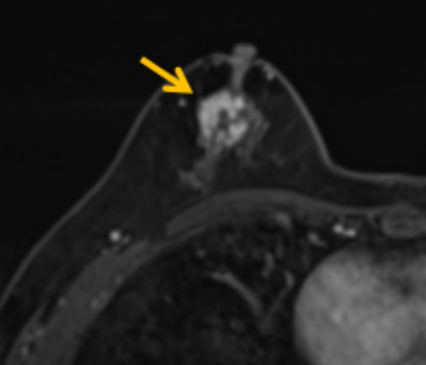

陳寶瑩評(píng)估圖像后發(fā)現(xiàn)病變?yōu)閮H僅在磁共振增強(qiáng)時(shí)顯示,為非腫塊樣病變,比較散,必須取得足夠多的組織才能確保病理檢查的準(zhǔn)確性,常用的核芯針活檢獲取的組織較少,因此最終確定了磁共振引導(dǎo)下行真空輔助抽吸旋切活檢。取得患者及家屬認(rèn)可后,陳寶瑩帶領(lǐng)團(tuán)隊(duì)開(kāi)始進(jìn)行術(shù)前準(zhǔn)備。

針對(duì)患者乳房小固定難度大這一問(wèn)題,陳寶瑩通過(guò)巧妙體位和固定器的調(diào)整,順利固定好乳房。經(jīng)過(guò)磁共振多模態(tài)掃描,陳寶瑩找出病變活性成分相對(duì)集中區(qū)域,精準(zhǔn)確定穿刺路徑,置入引導(dǎo)針、旋切針,到位后多角度旋切取出足量組織,拔除旋切針后即時(shí)行磁共振掃描,精準(zhǔn)取得組織且術(shù)區(qū)出血很少,遂加壓包扎,整個(gè)過(guò)程非常順利,旋切活檢后患者回家休息。兩天后隨訪(fǎng),李女士沒(méi)有任何不適,五天后皮膚上幾毫米的小切口已經(jīng)愈合。最終病理結(jié)果證實(shí)為乳腺導(dǎo)管原位癌,為早期乳腺癌,為患者后續(xù)針對(duì)性治療奠定了基礎(chǔ)。